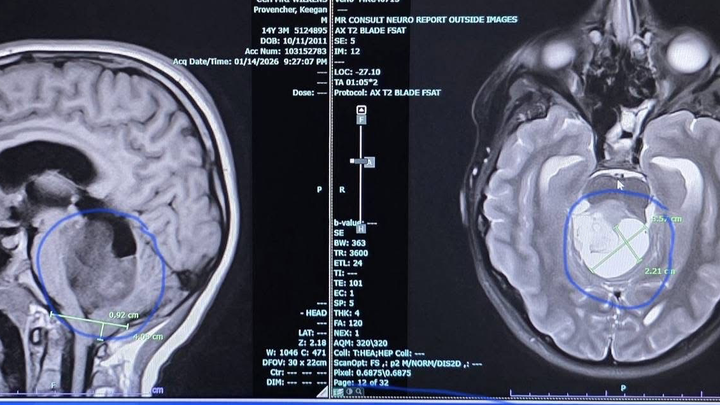

Two days ago, on Thursday, January 15th, I read something in my chart that no parent should ever have to read—that my 14-year-old son, Keegan, has a large brain tumor.

I called his doctor to push for an MRI. The MRI was ordered on Monday, and Wednesday morning we got the call that it was approved. Thursday night, while I was alone, I read the MRI results. I was reading something no parent should ever have to read.